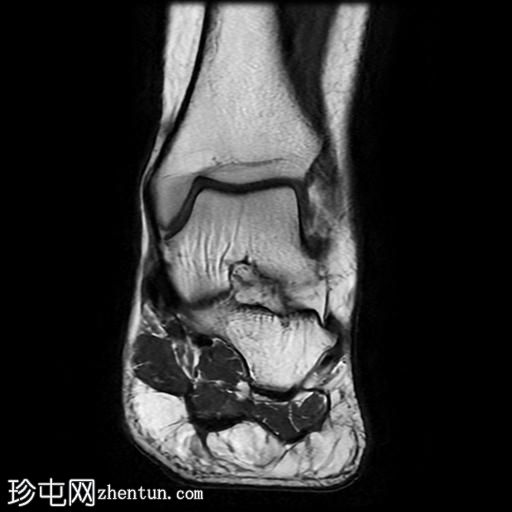

冠状位

T2加权像

冠状位PD加权像

脂肪抑制像

足底筋膜附着处可见足底跟骨骨刺,伴有下方局灶性骨髓水肿。

足底筋膜跟骨起点处可见增厚,并伴有实质内液体信号增高,尤其是在中内侧纤维,提示足底筋膜炎。

足底筋膜炎是指足底筋膜的炎症,是足跟痛最常见的原因。该病常伴有足底筋膜附着于跟骨处的骨刺,这会加重症状的严重程度并延长病程。